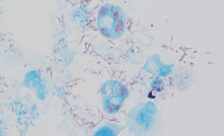

• El término rickettsia hace alusión a una bacteria parásita que produce, entre otras alteraciones de la salud, tifus y fiebre, mientras que la palabra rickettsiosis designa cualquier enfermedad causada por tales bacterias, según recoge el Diccionario de términos médicos, de la Real Academia Nacional de Medicina de...